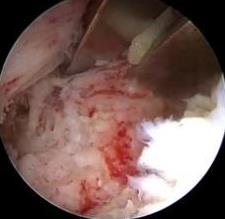

• 超声内镜引导下胃旁曲张静脉精准断流术治疗食管胃静脉曲张出血的疗效分析(附20例报告)

2025, 31(8):85-90. DOI: 10.12235/E20250036

摘要 (153) HTML (42) PDF 5.38 M (98) 评论 (0) 收藏

摘要:目的 探讨超声内镜引导下胃旁曲张静脉精准断流术治疗食管胃静脉曲张出血的疗效。方法 回顾性分析2024年1月1日-2024年12月31日于该院接受超声内镜引导下胃旁曲张静脉精准断流术治疗的20例肝硬化食管胃静脉曲张出血患者的临床资料,并评估治疗效果。结果 20例患者均顺利完成超声内镜引导下胃旁曲张静脉精准断流术;注射组织胶联合置入弹簧圈(16例)和单独注射组织胶(4例)均成功阻断胃旁来源的曲张静脉;所有患者均未发生穿孔、食管贲门狭窄、大出血、败血症和异位栓塞。1例单独注射组织胶的患者,术后胃旁曲张静脉少许渗血,经降低门静脉压力治疗3 d后好转,另1例单独注射组织胶患者,术后出现低热,抗感染3 d后体温恢复正常。结论 超声内镜引导下胃旁曲张静脉精准断流术治疗食管胃静脉曲张出血的临床疗效好,异位栓塞、大出血、感染和穿孔等并发症少,但仍需要密切随访,观察胃旁曲张静脉的排胶问题。